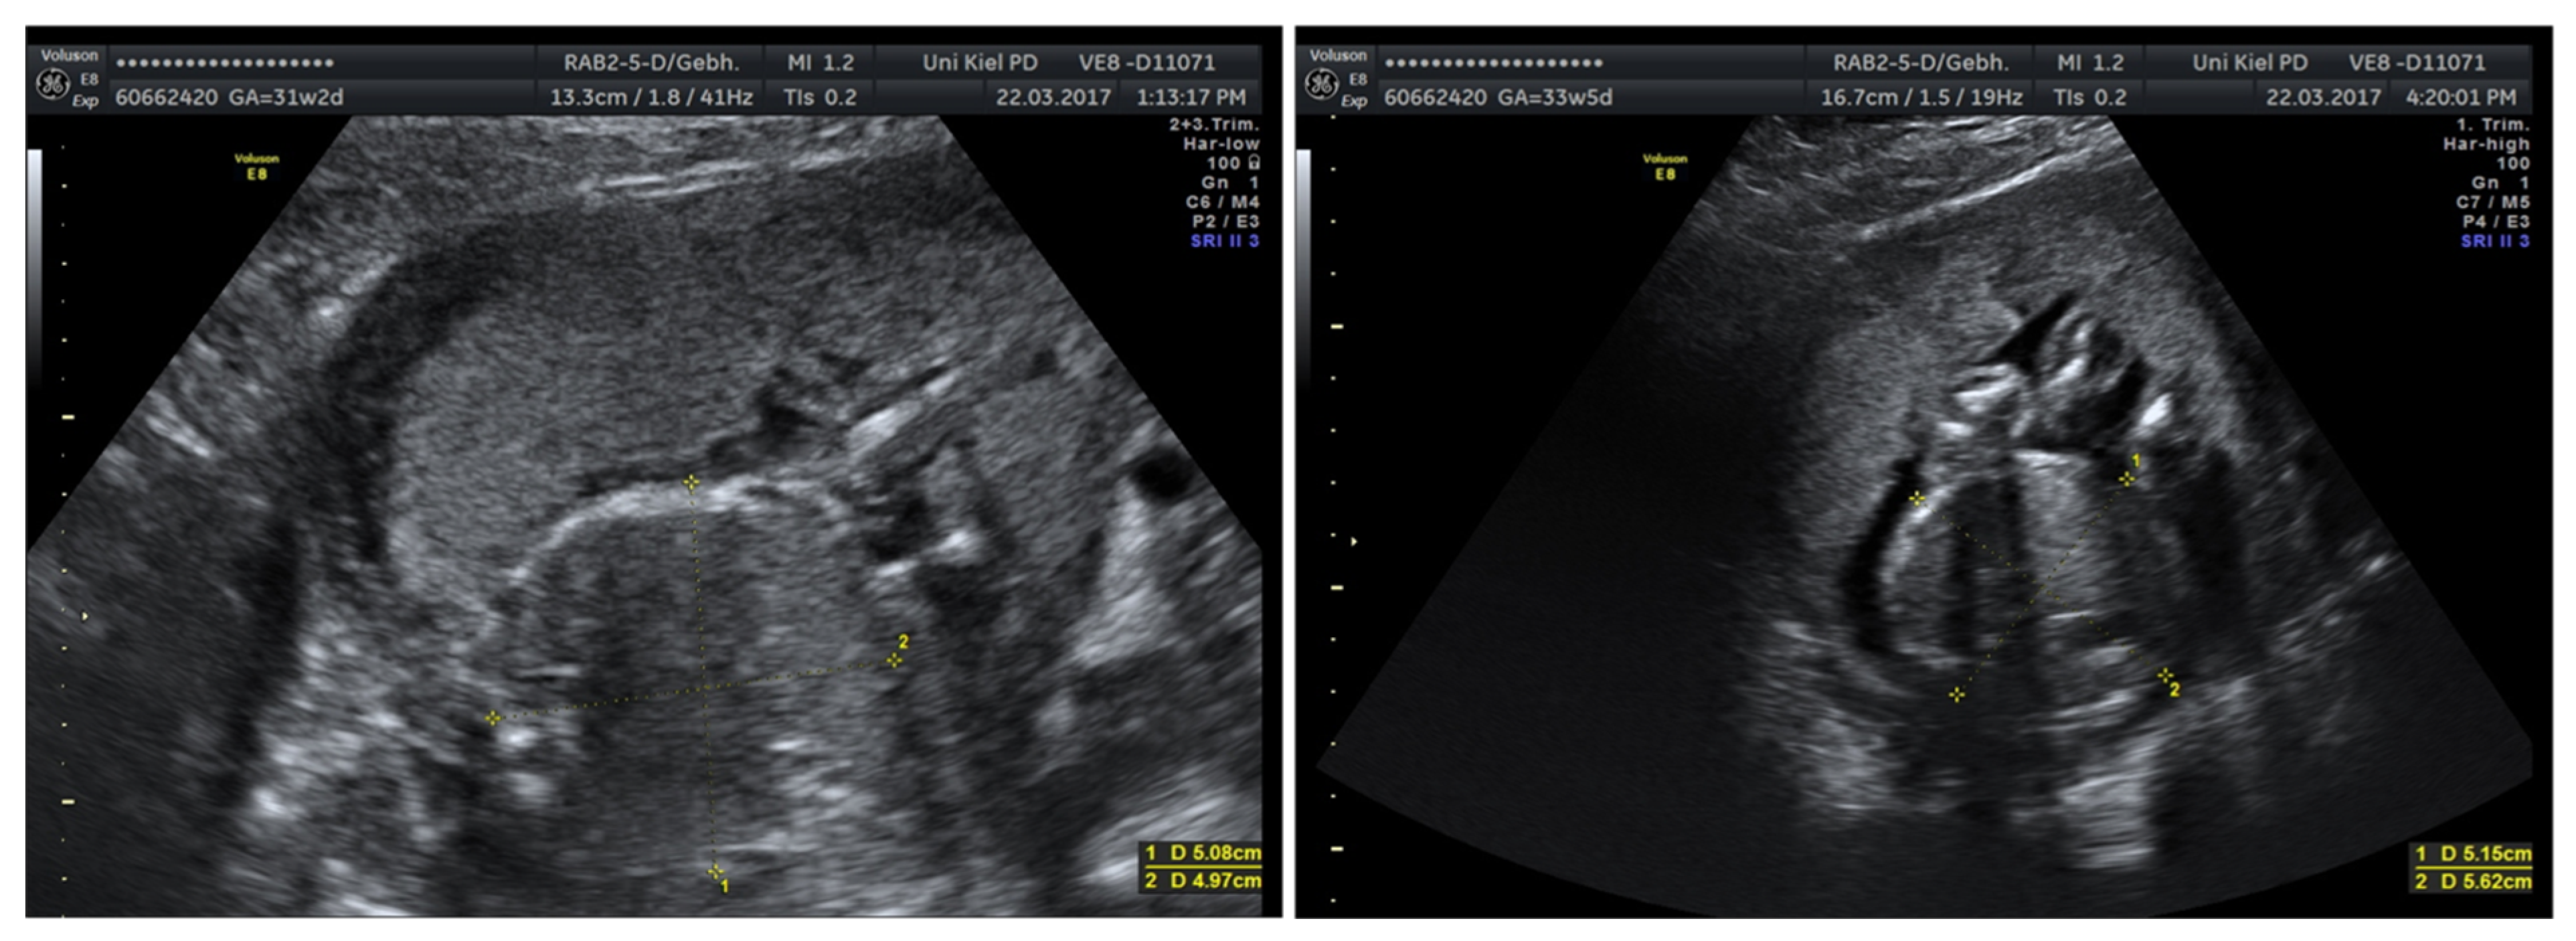

3.3.2. Fetal Growth Restriction

3.3.3. Urogenital Malformations

3.3.4. Chromosomal Aberrations and Severe Malformations